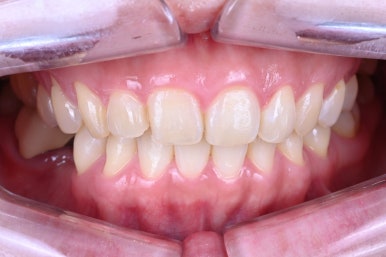

조금 더 멀리서 찍었더니 어두워 보이나? 싶으실텐데요.

어디에서 보아도 원래 치아의 어두웠던 색상은 보이지 않고,

치아가 너~무 말 이빨처럼 커보이지도 않고, 자연스러운 생김새를 갖고 있습니다.

아래 치아와 비교해보시면 더욱 더 뚜렷한 색상차이를 확인하실 수 있죠.

입안에 위치하고, 눈코입과 함께 보면 요 색상이 꽤나 자연스러움을 아실 수 있으실겁니다.

윗니와 아래이가 같이 있을 때 가장 도드라집니다.

치아의 가로-세로 비율이 좋아졌고, 좌우 대칭이 상당히 좋아졌습니다.

얼굴형과 어울리는 치아의 모양을 갖게되셔서, 참 결과가 좋았던 기억..^^